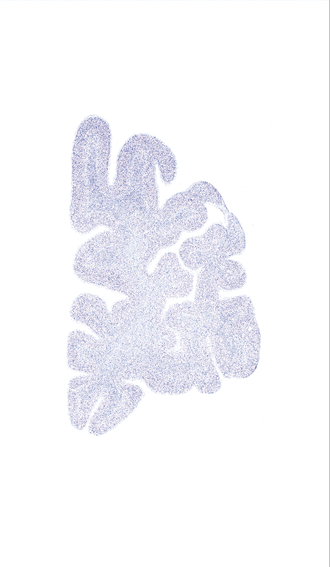

Hi-Resolution Sections · Cells (Nissl Staining) · Virtual Microscopy

Frontal sections (Nissl) from the Atlas Brain:

Slice ID:

r1-0500

Plate NR:

03

Position:

-47,9 mm